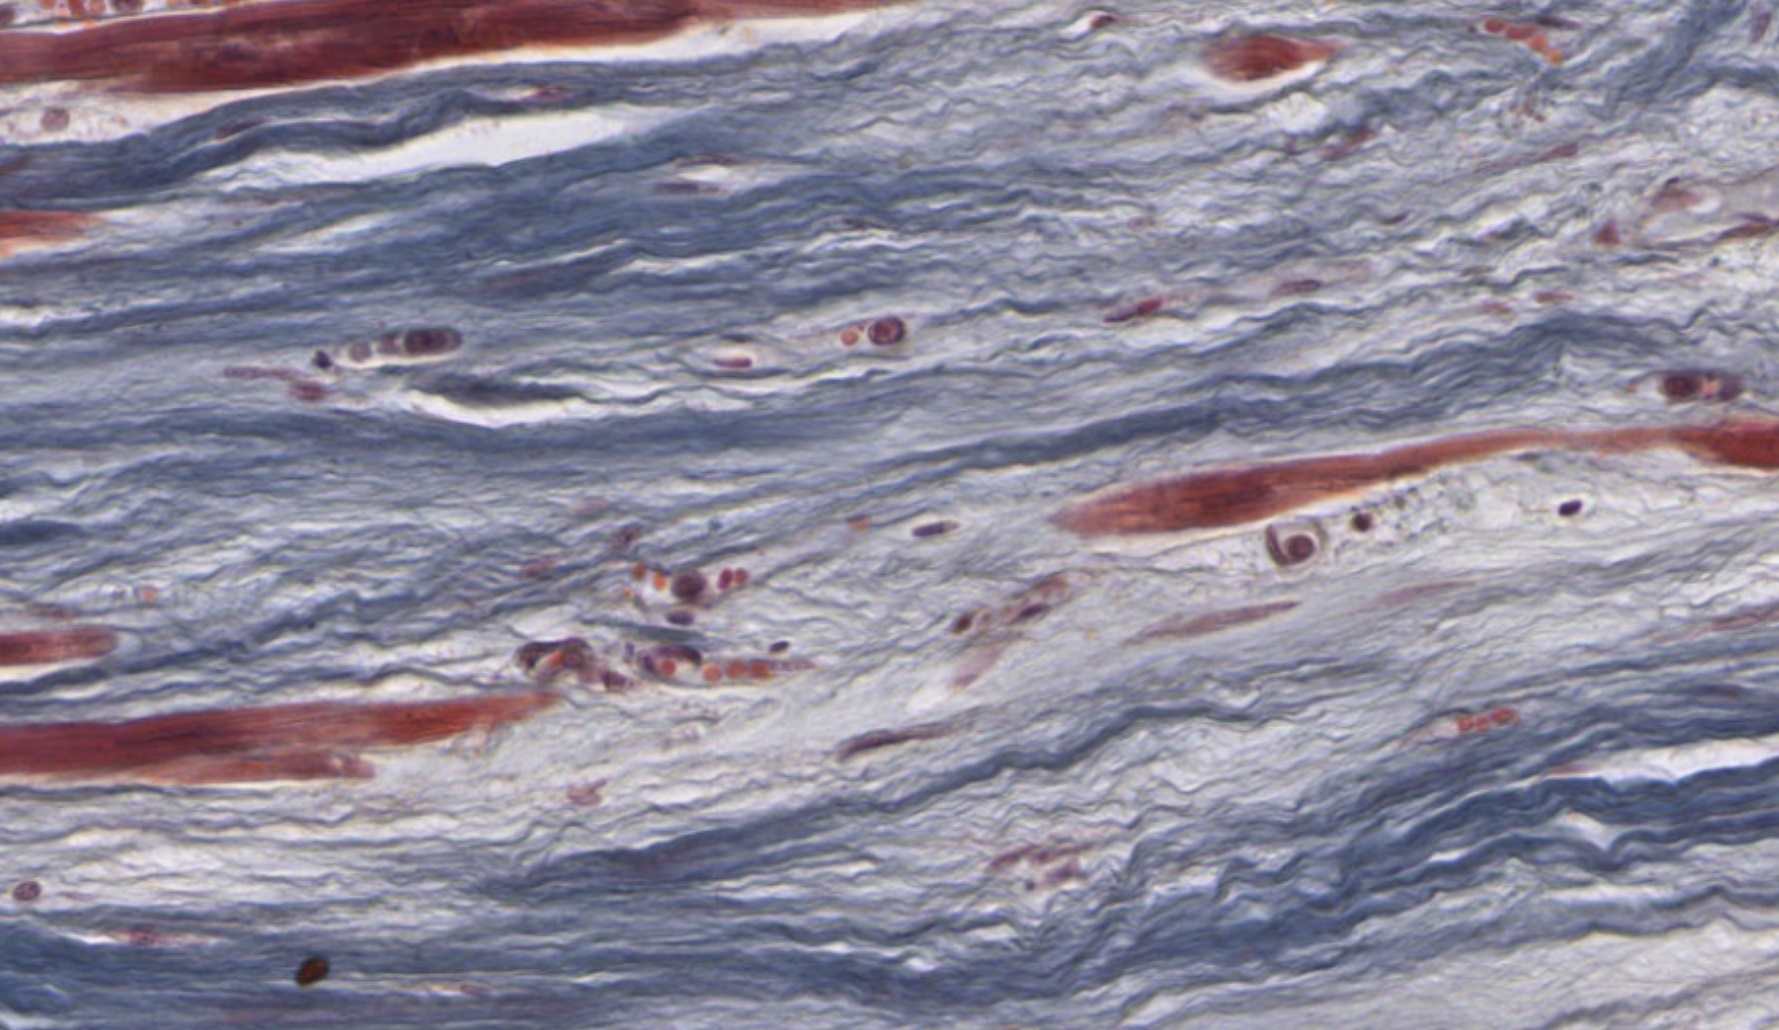

Elastic Artery Wall β€” Slide 303 Β· Verhoeff Stain β€” Two tissues on this slideThis single slide gives you both smooth muscle and elastic CT at once. Orient yourself by finding the lumen (open central space), then work outward. The Verhoeff stain has turned elastin fibers unmistakably black β€” everything else appears lighter. The smooth muscle cells are the spindle-shaped cells embedded between those black lines in the tunica media.

Elastic artery wall Verhoeff stain

Elastic artery wall Β· Verhoeff stain Β· Slide 303 Β· bettybroadbent.com

Click each numbered chip to reveal the labeled structure

Don't confuse elastin and collagen. On Verhoeff stain, elastin = black and wavy (squiggly). Collagen would be pink on H&E. On this slide, every black lamina is elastin β€” they are the elastic CT. The smooth muscle cells are the lighter spindle-shaped cells between them.

Clinical Connection β€” Aortic Aneurysm

An aortic aneurysm is a dangerous dilation of the aortic wall caused by breakdown of the elastic laminae you just labeled β€” from hypertension, Marfan syndrome (fibrillin-1 mutation), or atherosclerosis. The smooth muscle may still look intact, but without the elastic scaffold, the wall can't withstand systolic pressure. On Verhoeff stain, you would see those beautiful parallel black lines becoming fragmented, interrupted, or absent in the affected region.